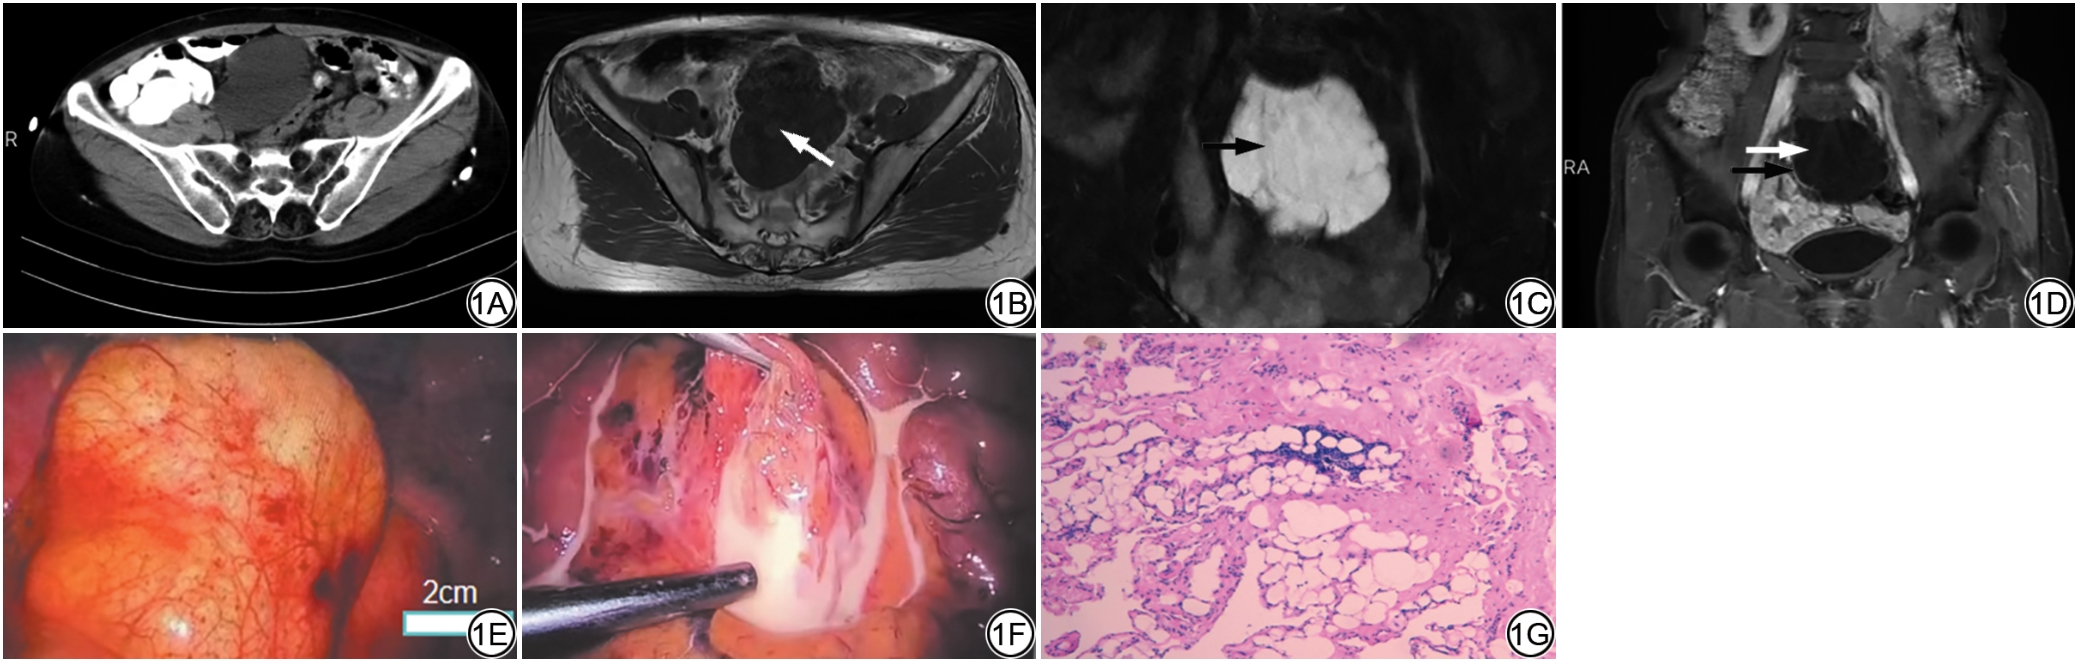

于次日行盆腔CT平扫示:盆腔内见大小约10 cm×6 cm囊性低密度包块,形态欠规则,边界尚清,密度均匀,囊液CT值约10 HU,囊壁厚度<2 mm,无结节及钙化,与邻近肠管脂肪间隙清晰,无浸润征象(图1A)。CT诊断:肠系膜囊肿或囊性淋巴管畸形,请结合临床。后于第三日行MRI平扫同时增强检查示:盆腔内见大小约10 cm×8 cm巨大囊性包块,形态欠规则,T1WI呈低信号,T2WI呈高信号(未与脑脊液信号对比),内见低信号分隔,囊壁薄且光整,未见壁结节(图1B1C),增强扫描动脉期、门脉期及延时期囊壁呈轻度强化(图1D),与邻近肠管脂肪间隙清晰,无浸润征象,考虑囊性淋巴管畸形或肠系膜囊肿。排外手术禁忌证后行腹腔镜下肠系膜病损切除术,术中探查:部分网膜及结肠系膜粘连于左侧盆壁,与左侧输卵管、卵巢粘连,距回盲部约110 cm处可见直径约10 cm囊肿,位于肠系膜内,活动尚可,呈多房样改变,刺破囊壁,见乳白色液体(图1E1F)。术后肿块取活检,其镜下形态:病灶由大小不等的腔隙组成,囊壁薄,部分呈囊状扩张,囊壁衬覆单层扁平内皮细胞,囊腔内充满蛋白性液体,含淋巴细胞(图1G)。免疫组化:D-24(+),CD31(+),Prox1(+),SMA(+),结合免疫组化最终病理诊断为:肠系膜囊性淋巴管畸形。

图1  女,56岁,肠系膜淋巴管畸形。1A:CT示盆腔内见囊性包块,密度均匀,CT值约10 HU,与邻近肠管分界清楚;1B:盆腔内包块,T1WI呈低信号,内混杂蛋白性稍高信号(白箭),边界清楚,与邻近肠管分界清楚;1C:冠状位T2WI脂肪抑制示肿块呈高信号,内见低信号分隔(黑箭),未见壁结节,边缘欠规整;1D:增强扫描(动脉期)病灶囊性成分未见强化(白箭),囊壁及分隔轻度强化(黑箭);1E~1F:术中可见病灶位于肠系膜内,活动尚可,呈多房样改变,边缘光整(1E),刺破囊壁,囊内见乳白色液体(1F);1G:术后病理示病灶由大小不等的腔隙组成,囊壁薄,部分呈囊状扩张,囊壁衬覆单层扁平内皮细胞,囊腔内充满蛋白性液体,含淋巴细胞。

Fig. 1  Female, 56 years old, mesenteric lymphatic malformation. 1A: A cystic mass is seen in the pelvic cavity with uniform density and a CT value of approximately 10 HU, it is clearly demarcated from the adjacent intestinal tubes. 1B: Pelvic mass, presenting as low signal intensity on T1WI with slightly high signal in confounding proteins (white arrow), clear boundaries, and distinct demarcation from adjacent intestinal tubes. 1C: Coronal T2WI fat saturation shows the mass with high signal intensity, with low signal intensity septations inside (black arrow), no mural nodules are seen, and the margin is irregular. 1D: The cystic components of the enhanced scan lesion (arterial phase) showed no enhancement (white arrow), while the cyst wall and septa showed mild enhancement (black arrow). 1E: The lesion is located within the mesentery, the activity is still moderate, presenting as a multi-lobulated change with a smooth edge. 1F: The capsule wall is punctured, and a milky white liquid can be seen inside the capsule. 1G: The lesion is composed of cavities of varying sizes, with thin cyst walls, some of them are cystically dilated, the cyst walls are lined with a single layer of flat endothelial cells, and the cyst cavities are filled with proteinaceous fluid containing lymphocytes.